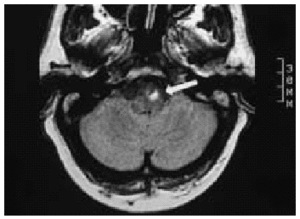

Varón de 71 años de edad, que fue ingresado por presentar un cuadro de dolor precordial de características coronarias en el ECG, presentaba una corriente de lesión subepicárdica inferior y lateral baja y escaso crecimiento de ondas R en las precordiales derechas por probable necrosis anteroseptal antigua. Se procede a la realización de una fibrinolisis con tenecteplasa, manteniendo perfusión de heparina sódica, antiagregación con ácido acetilsalicílico y nitritos. A las 4 h de la fibrinolisis aparece diplopía y afección del VI par craneal izquierdo; se realizó una tomografía computarizada craneal que mostró una dudosa imagen hiperintensa localizada en troncoencéfalo de 1 ml. Con objeto de completar el estudio se realizó una resonancia magnética nuclear craneal (figs. 1 y 2), que mostró una lesión ovalada de 1 cm en la unión bulboprotuberancial izquierda hiperintensa (con centro más hipointenso, en relación con la evolución normal de los componentes de la hemoglobina). El diagnóstico fue de hematoma intraparenquimatoso en la unión bulbomedular izquierda. La evolución posterior fue satisfactoria, con restitución ad integrum a los 2 meses. El juicio clínico fue de hematoma de la unión bulboprotruberancial secundario a fibrinolisis.

Figura 2.